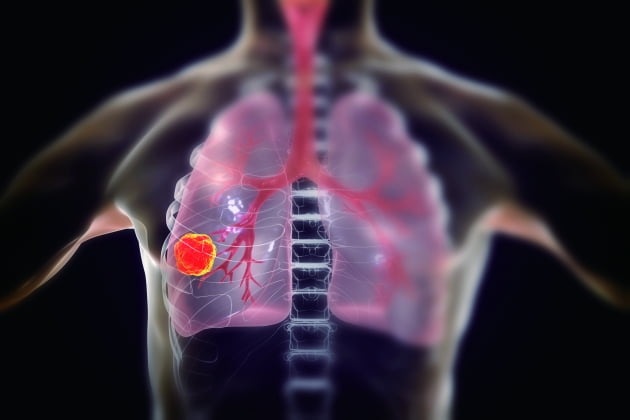

가슴 통증

폐암의 초기증상 중에 흉통이 있습니다. 폐암 환자의 약 1/3이 흉통을 호소합니다. 흉통의 원인은 폐 가장자리에 종양이 형성되어 암세포를 생성하고 흉벽과 흉막에 침착되어 통증을 유발하는 것입니다.

흉통의 원인은 여러 가지가 있을 수 있지만, 오늘날 우리가 다루고 있는 폐암으로 인한 흉통은 경미한 통증보다는 지속적인 따끔거림과 둔한 통증을 동반한다는 점에 유의하시기 바랍니다. 또한 암은 흉막이나 흉벽 대신 갈비뼈로 퍼져 통증을 유발할 수 있습니다. 종양은 주변 조직 세포를 자극할 수 있으므로 계속해서 통증을 유발하는 경우 의사의 진찰을 받는 것이 좋습니다.